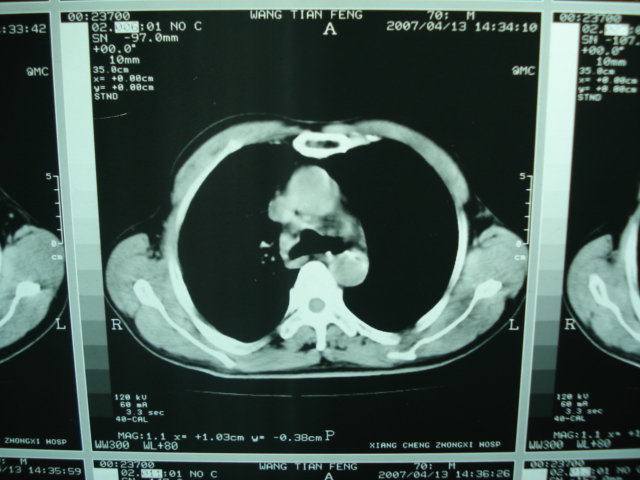

以下是引用狙击手在2007-4-18 20:17:00的发言:[br]原:2007/1/22号ct片:右肺上叶可见片状、云雾状高密度影,右肺上叶后段可见三角形高密度影,尖端指向肺门,右肺上叶后段支气管壁不规则增厚,管腔不规则增厚,纵隔未见肿大淋巴结.[br] 今ct:右肺上叶片状影增大,右肺上叶后段不张及右肺上叶后段支气管壁不规则增厚未见变化,右肺下叶背段支气管壁不规则增厚.[br] 如果考虑肺结核,但从临床证据看竟然没有一项支持肺结核,不知患者是否已经过正规抗结核治疗。没有的话,3个月了前后片看起来变化不大,似乎有不太符合肿瘤征象,不知患者是否抗炎治疗过,下叶支气管增粗还是要高度警惕,同意楼主意见,将常规病理,生化检查再做一遍。[br]

以下是引用狙击手在2007-4-18 20:17:00的发言:[br]原:2007/1/22号ct片:右肺上叶可见片状、云雾状高密度影,右肺上叶后段可见三角形高密度影,尖端指向肺门,右肺上叶后段支气管壁不规则增厚,管腔不规则增厚,纵隔未见肿大淋巴结.[br] 今ct:右肺上叶片状影增大,右肺上叶后段不张及右肺上叶后段支气管壁不规则增厚未见变化,右肺下叶背段支气管壁不规则增厚.[br] 如果考虑肺结核,但从临床证据看竟然没有一项支持肺结核,不知患者是否已经过正规抗结核治疗。没有的话,3个月了前后片看起来变化不大,似乎有不太符合肿瘤征象,不知患者是否抗炎治疗过,下叶支气管增粗还是要高度警惕,同意楼主意见,将常规病理,生化检查在做一遍。[br]